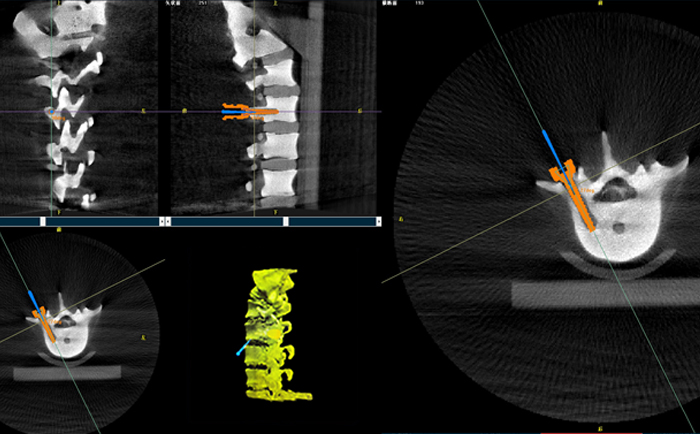

以椎弓根螺釘置入手術為例,傳統(tǒng)手術為了準確定位,需要將其多次進出反復選擇,增加了神經(jīng)損傷與螺釘損壞的風險。但外科手術機器人可通過術前規(guī)劃把手術入路、方向、釘子深度都規(guī)劃好,基本做到一步到位,讓手術更加安全。

手術開始前,外科手術機器人與3D C形臂對患者的患處進行了一次掃描,做到“知己知彼”;接著電腦系統(tǒng)為每一顆螺釘設計出前進的路徑;隨后,“穩(wěn)如泰山”的機器人之手——機械臂,開始為每條路徑掃除障礙,猶如鋪設火車軌道;最后沿標準路徑置入螺釘,猶如火車行駛在車軌之上,最終準確置入螺釘。

外科手術機器人3D影像

普愛醫(yī)療的外科手術機器人經(jīng)國家藥監(jiān)局批準,作為第三類醫(yī)療器械開始上市并應用于臨床,主要用于椎弓根螺釘內固定術、經(jīng)皮穿刺椎體成形術等術式(包括頸椎、腰椎、胸椎等)等脊柱外科手術。輔助準確定位植入物或手術器械,精度達到亞毫米級,尤其對微創(chuàng)手術、高風險手術具有明顯優(yōu)勢,可有效降低手術風險、減少手術并發(fā)癥。